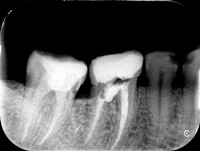

Nieczęsty przypadek trzykanałowej dolnej piątki, przed i po reendo.

Przed i po reendo.